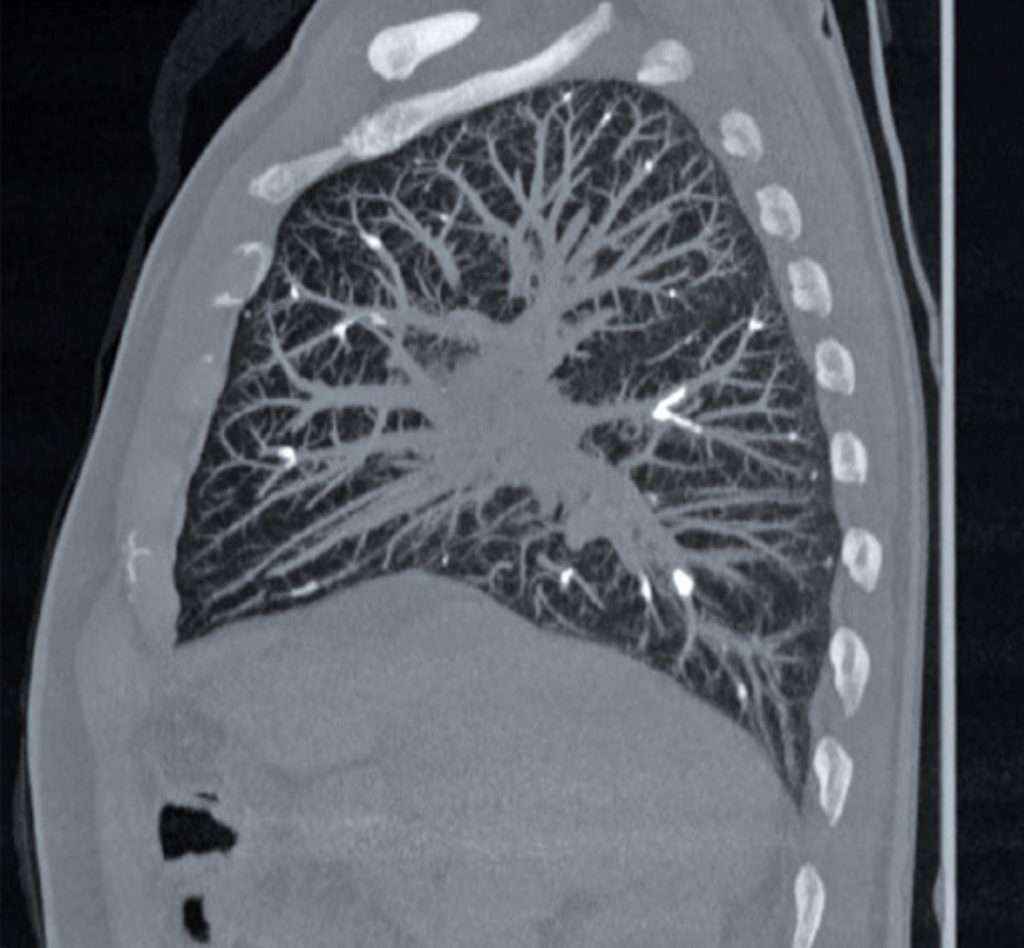

This was a 65-year-old male patient with cirrhosis who experienced sudden dyspnea and thoracic pain few hours after underwent endoscopic sclerotherapy of gastric and esophageal varices by cyanoacrylate solution injection and Lipiodol ® . The patient underwent computed tomography of the chest ( ).

Figure 3

Tomography without contrast in sagittal section, in the mediastinum window, showing the same findings